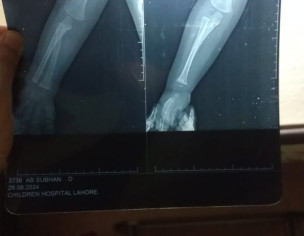

My Child Fell from Bed, and we went to childeren hospital in lahore, they ask for Xray and after analysing they said its a minor fracture that does not need any plaster, Later we went to Ittefaq Hospital, and their dr asked for new Xray, he also said their is fracture in Arm, So it needs to be plaster. What i am unable to understand is the price the asked for it, Dr said it will take 50 to 60K for Plaster. Does is it really cost that much??. i have shared Xrays, Kindly comment your thought !. Thanks,

minor fracture ha .50k ma to surgery hojati ha.plaster 4k tk hojaega maximum